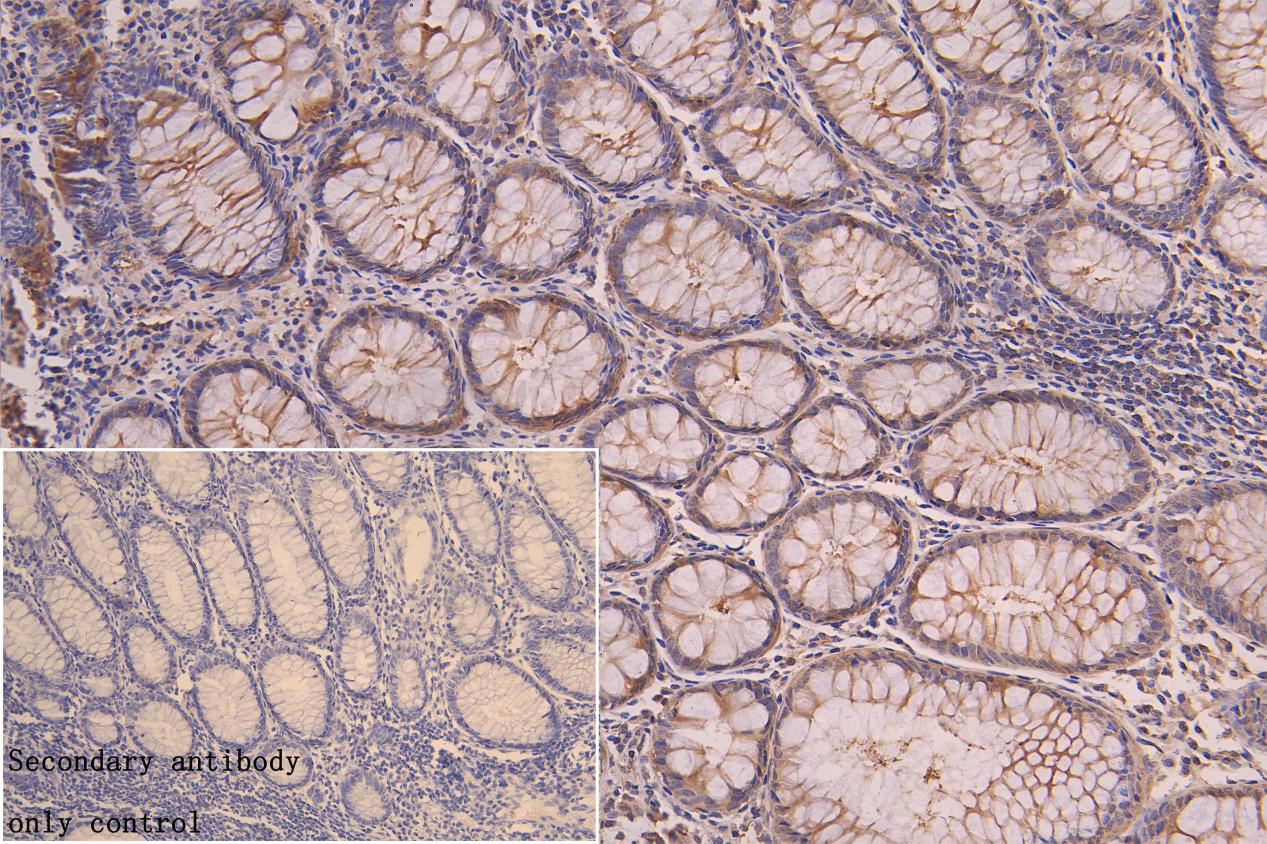

IHC image of CSB-RA616077A0HU diluted at 1:50 and staining in paraffin-embedded human colorectal cancer performed on a Leica BondTM system. After dewaxing and hydration, antigen retrieval was mediated by high pressure in a citrate buffer (pH 6.0). Section was blocked with 10% normal goat serum 30min at RT. Then primary antibody (1% BSA) was incubated at 4°C overnight. The primary is detected by a Goat anti-rabbit polymer IgG labeled by HRP and visualized using 0.05% DAB. Secondary antibody only control: uses 1% BSA instead of primary antibody